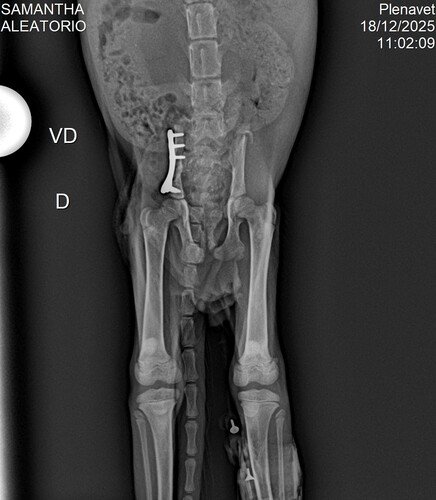

A cirurgia foi um sucesso! Hoje, o Madruguinha está estável, ativo, comendo, interagindo e, aos poucos, retomando a vida que quase lhe foi tirada. Ele venceu a parte mais dura da história, mas ainda precisa de apoio.